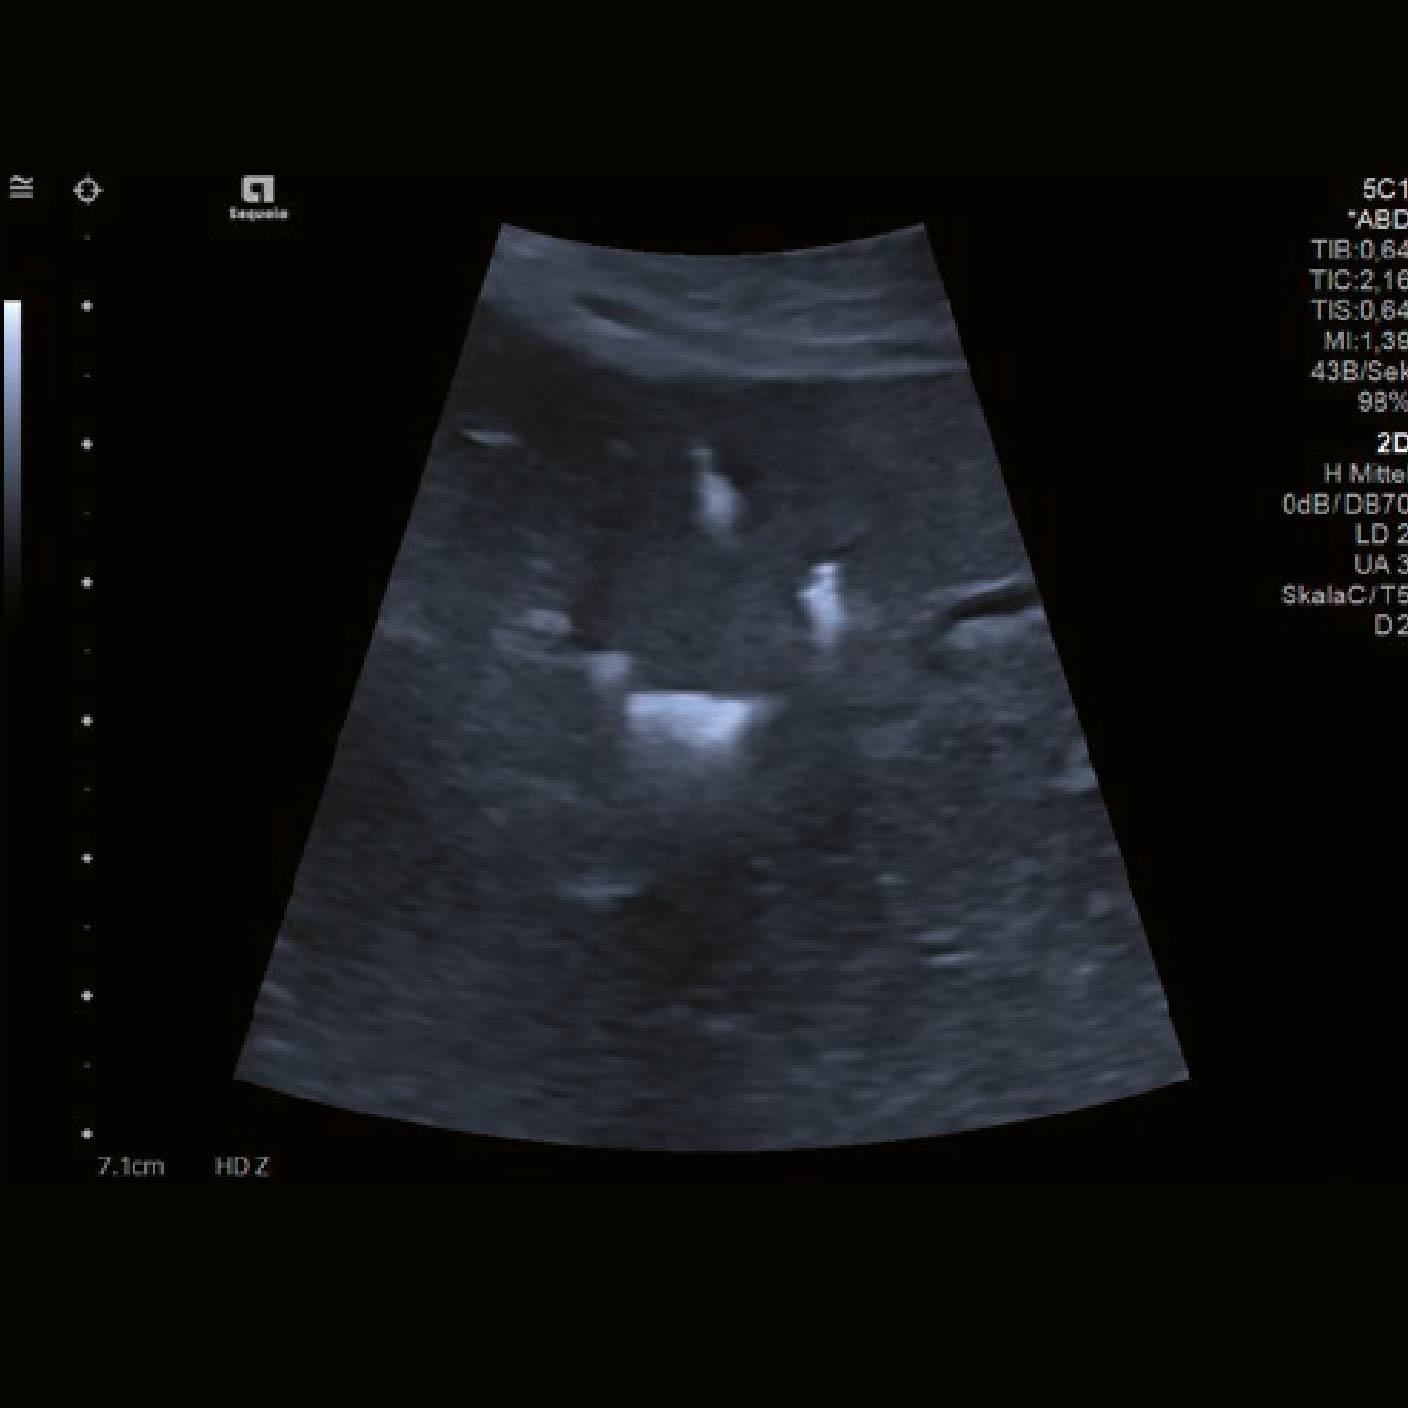

Se realizó una ecografía 2D de la región de interés (ROI). Además de los clips quirúrgicos, previamente identificados en el área tratada, la ecografía mostró parénquima hepático con baja conspicuidad en comparación con el tejido circundante [Fig. 1].